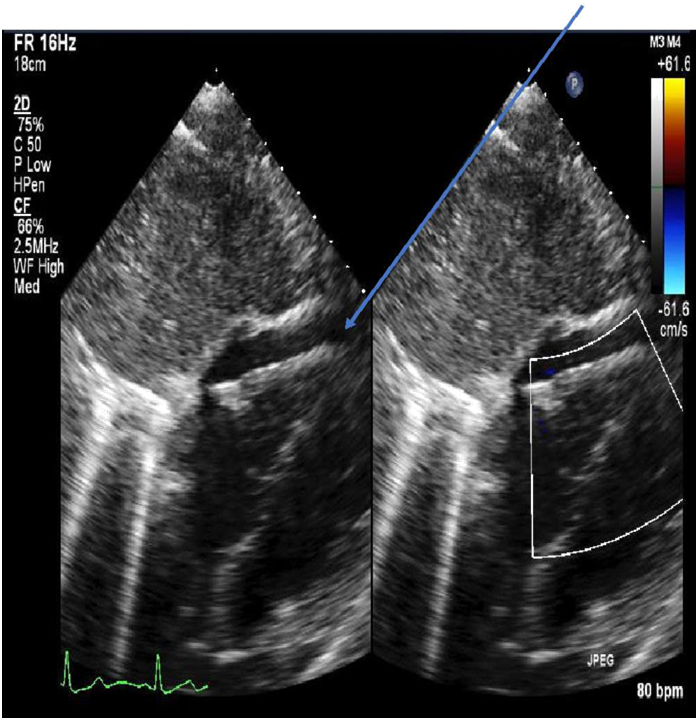

ECG revealed sinus tachycardia and right axis deviation without ST-T changes (Figure 1.). Laboratory studies, summarized in Table 1, revealed a mild normocytic, normochromic anemia and a considerably elevated serum troponin I level. Chest radiography (Figure 2) revealed a non-specific mild left perihilar/lingular area of atelectasis or infiltrate. Given her history of fever, the patient underwent technetium labeled white blood cell (WBC) scanning, prior to the onset of her chest pain, which revealed intense labeled WBC uptake at the left ventricular myocardium consistent with myopericarditis (Figure 3). A transthoracic echocardiogram (Figure 4) revealed normal right and left ventricular (left ventricular ejection fraction of 55-60 %) and a small pericardial effusion.

Figure 4 Transthoracic echocardiography (arrow indicating small pericardial effusion).